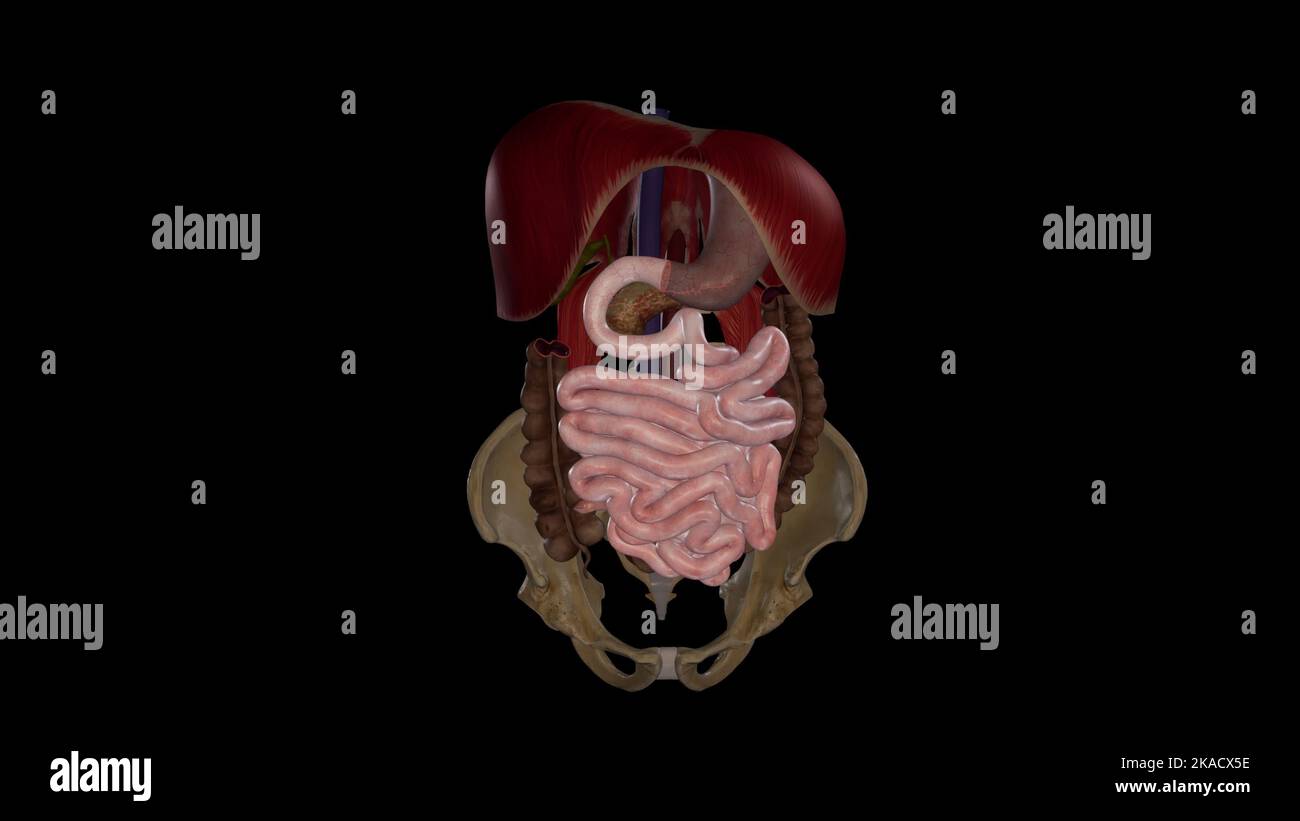

RF2GCN749–La vista scout (topogramma) per una TC dell'addome e del bacino con contrasto endovenoso. Immagini di riferimento per l'acquisizione di una serie TC assiale.